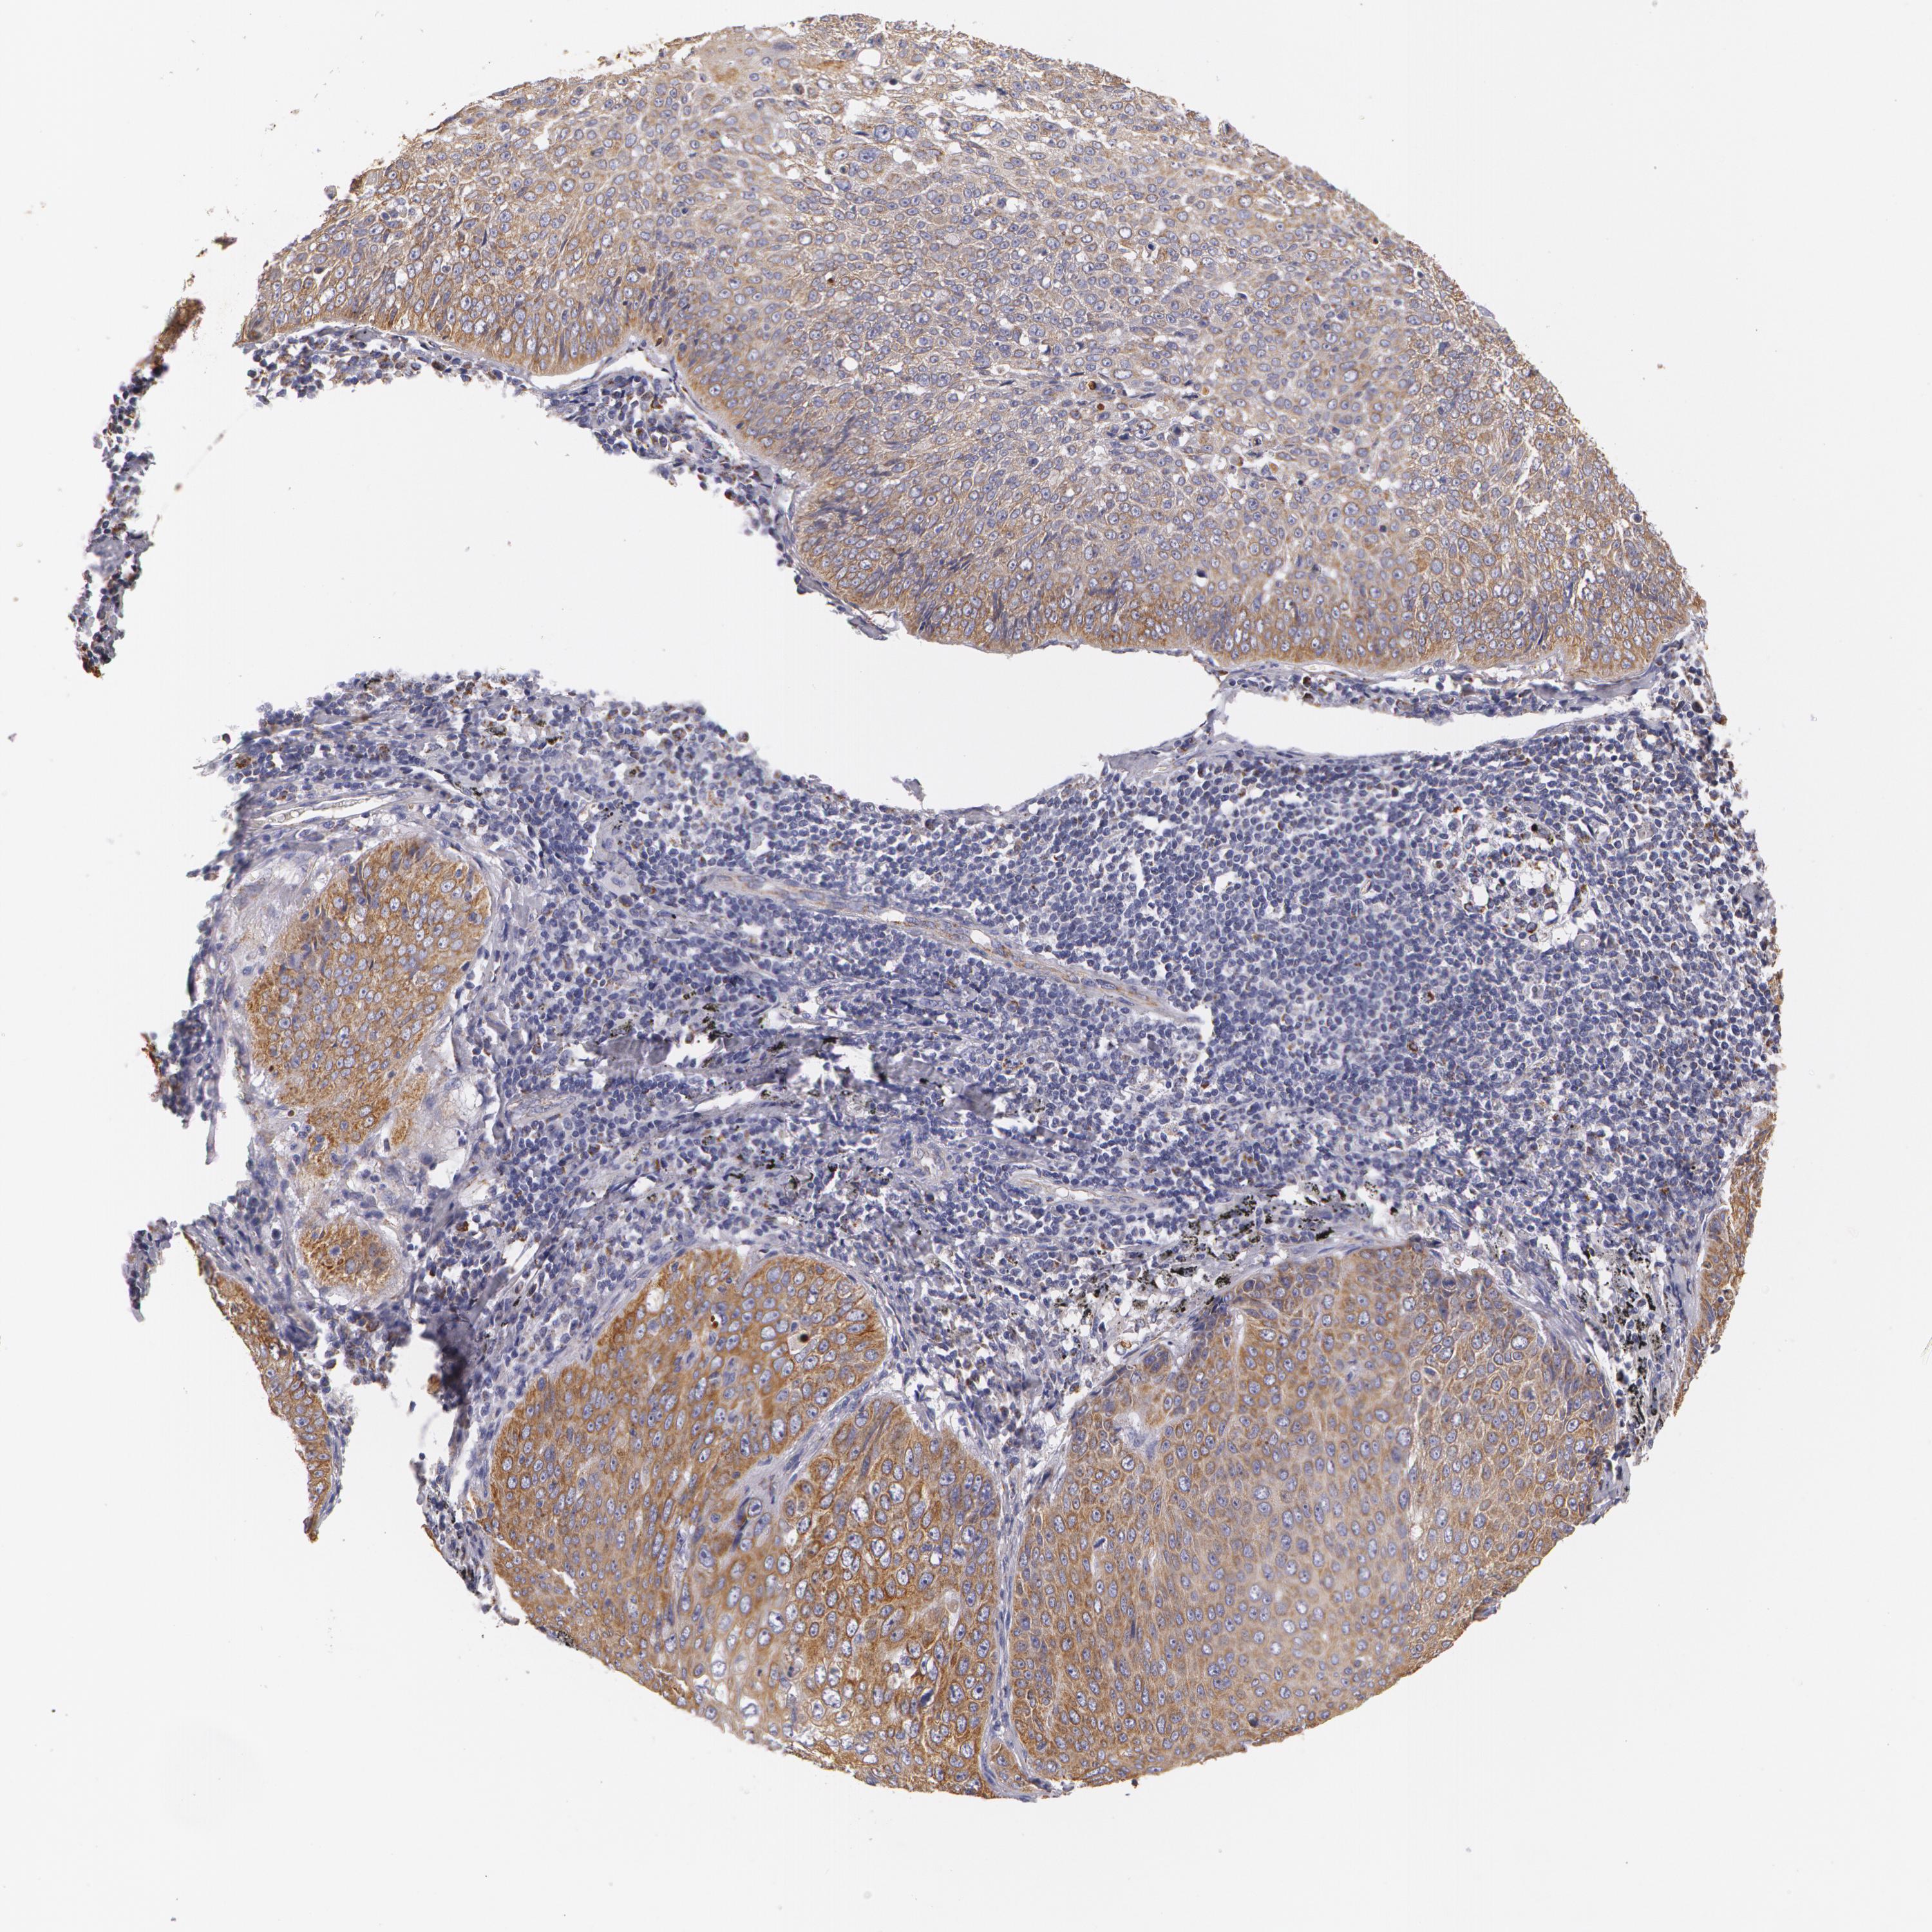

LUNG ADENOCARCINOMA (VALIDATION) - Interactive survival scatter ploti

The Survival Scatter plot shows the clinical status (i.e. dead or alive) for all individuals in the patient cohort, based on the same data that underlies the corresponding Kaplan-Meier plots. Patients that are alive at last time for follow-up are shown in blue and patients who have died during the study are shown in red.

The x-axis shows the expression levels (FPKM) of the investigated gene in the tumor tissue at the time of diagnosis. The y-axis shows the follow-up time after diagnosis (years). Both axes are complimented with kernel density curves demonstrating the data density over the axes. The top density plot shows the expression levels (FPKM) distribution among dead (red) and alive patients (blue). The right density plot shows the data density of the survived years of dead patients with high and low expression levels respectively, stratified using the cutoff indicated by the vertical dashed line through the Survival Scatter plot. This cutoff is automatically defined based on the FPKM cutoff that minimizes the p-score. The cutoff can be changed by dragging the vertical line or by entering a cutoff value in the square labeled "Current cut-off".

Under the Survival Scatter plot the p-score landscape (black curve; left axis) is shown together with dead median separation (red curve; right axis). Dead median separation is the difference in median mRNA expression between patients who have died with high and low expression, respectively. It is calculated as follows: median FPKM expression of dead patients with high expression - median FPKM expression of dead patients with low expression. This is intended to aid the user in visually exploring custom cutoffs and the associated p-scores and dead median separation.

Individual patient data is displayed and can be filtered by clicking on one or more of the category buttons on the top of the page. Categories describing expression level and patient information include: high, low, alive, dead, female, male and tumor stages. The scale of the x-axis can be toggled between linear and log-scale by clicking on the "x log" button. Mouse-over function shows TCGA ID, patient information and mRNA expression (FPKM) for each patient.

& Survival analysisi

Kaplan-Meier plots summarize results from analysis of correlation between mRNA expression level and patient survival. Patients were divided based on level of expression into one of the two groups "low" (under cut off) or "high" (over cut off). X-axis shows time for survival (years) and y-axis shows the probability of survival, where 1.0 corresponds to 100 percent.

KRT18 is not prognostic in Lung Adenocarcinoma (validation)

: 306.96